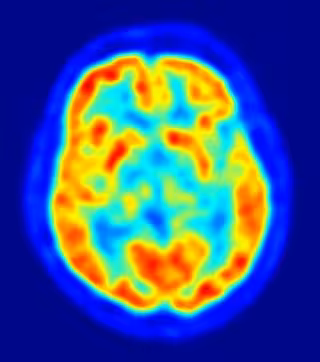

El autismo modifica la estructura molecular del cerebro

Investigadores de la Universidad de California en Los Ángeles (UCLA), en Estados Unidos, han conseguido detectar la primera huella física del autismo, después de haber observado diferencias en la estructura molecular del cerebro de quienes lo padecen, según un estudio que publica la revista 'Nature'.

Tras haber identificado previamente tres áreas cerebrales potencialmente relacionadas con el autismo, el grupo se concentró en la corteza cerebral, la parte más evolucionada del cerebro humano.

Al medir los niveles de expresión génica en la corteza cerebral, observaron diferencias consistentes a la hora de codificar la información entre los cerebros autistas y los de personas sanas.

Cuando los científicos compararon los lóbulos frontal y temporal en los cerebros sanos, vieron que más de 500 genes se expresaban en diferentes niveles en las dos regiones. En el cerebro autista, en cambio, apenas había diferencias.

"En un cerebro sano, cientos de genes se comportan de manera diferente en cada región, no así en el cerebro autista", explica.

Además, también observaron que los cerebros autistas mostraron una caída en los niveles de los genes responsables de la función neuronal y la comunicación, al tiempo que aumentaban los genes implicados en la función inmune y la respuesta inflamatoria.